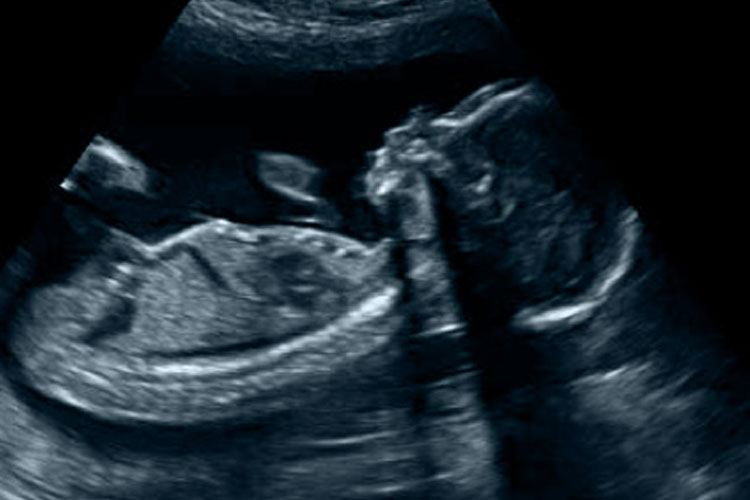

| 20 Weken Echo Limburg Echocentrum Het Lichtpunt |